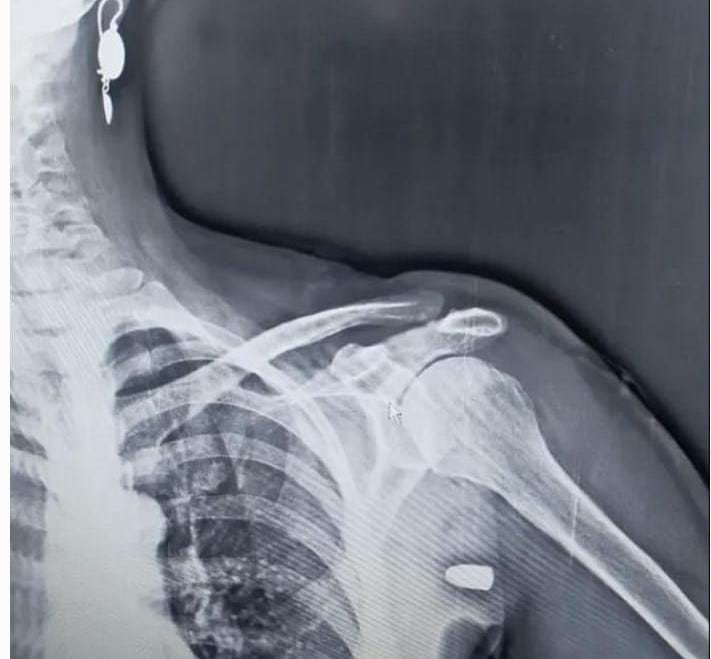

İlçenin Karaağaç Mahallesi yakınlarındaki Hırsafa Yaylası'nda ot biçen Asiye İnce (59), önceki gün yayla evinin yanındaki bahçede ot biçerken sol omuz bölgesinden giren yorgun mermi ile yaralandı. İnce, yakınlarının yardımıyla Tonya Devlet Hastanesi'ne kaldırıldı. Burada yapılan müdahalenin ardından Vakfıkebir Devlet Hastanesi'ne sevk edilen İnce'nin omuzundaki mermi çekirdeği ameliyatla çıkartıldı. Asiye İnce hastaneden taburcu edilirken, başından geçenleri anlattı.

Asiye İnce'nin eşi Yakup İnce (61) ise "O gün bende hastanedeydim. Telefonum çaldı hayırdır dedim. Orda dur vuruldum geliyorum dedi. Şaşırdım kimseyle alıp veremediğim yok. Hastaneye geldiler kurşun şah damarına 1.5 santim kala girmiş. Kalbe yakın bir noktada girmiş. Silahın eğitimli kişilere verilmesini istiyorum. Eğitimsiz her önüne gelenin silah almamasını istiyorum. Yaylada hiç böyle bir şeye rastlamamıştık. Allah'ıma bin şükür eşimi bana bağışladı" ifadelerini kullandı.